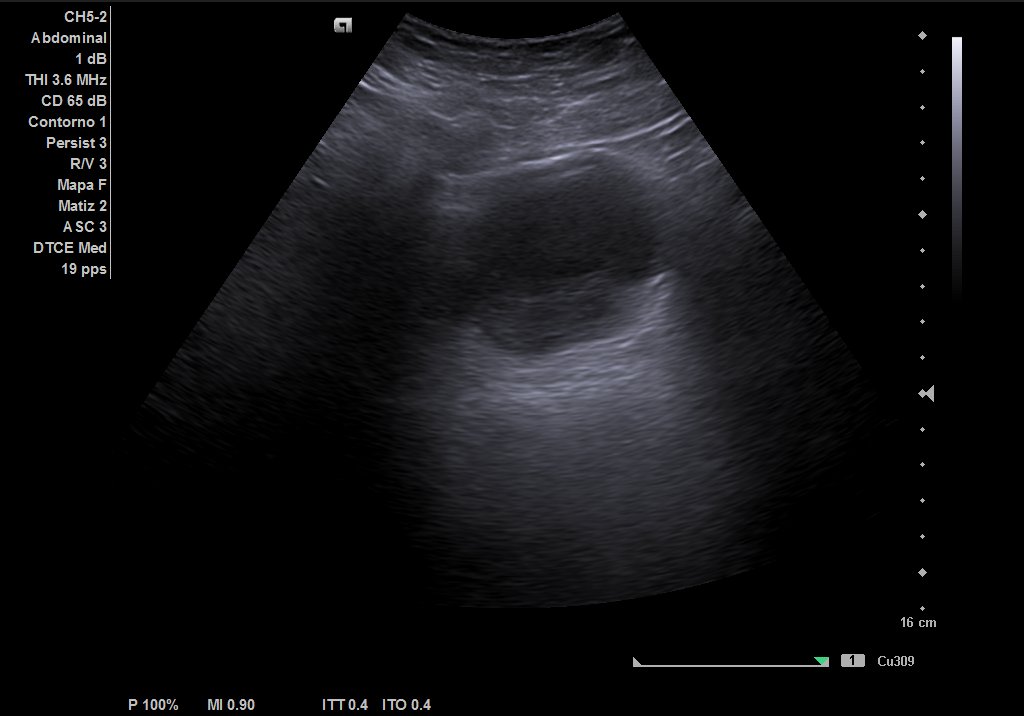

Descripción de los hallazgos ecográficos y las imágenes más relevantes para la resolución del caso

Ecografía urinaria: vejiga bien replecionada, observándose masa en trígono de 20 x 12 mm. Riñón derecho con dilatación pielocalicial moderada, sin hidronefrosis. Riñón izquierdo sin alteraciones reseñables.

Ecografía reglada: ureterohidronefrosis grado III secundaria a lesión en uréter medio-distal. Vejiga parcialmente replecionada con material ecogénico en suelo vesical con aparente doppler color e interior. Posible coágulo vs lesión subyacente.